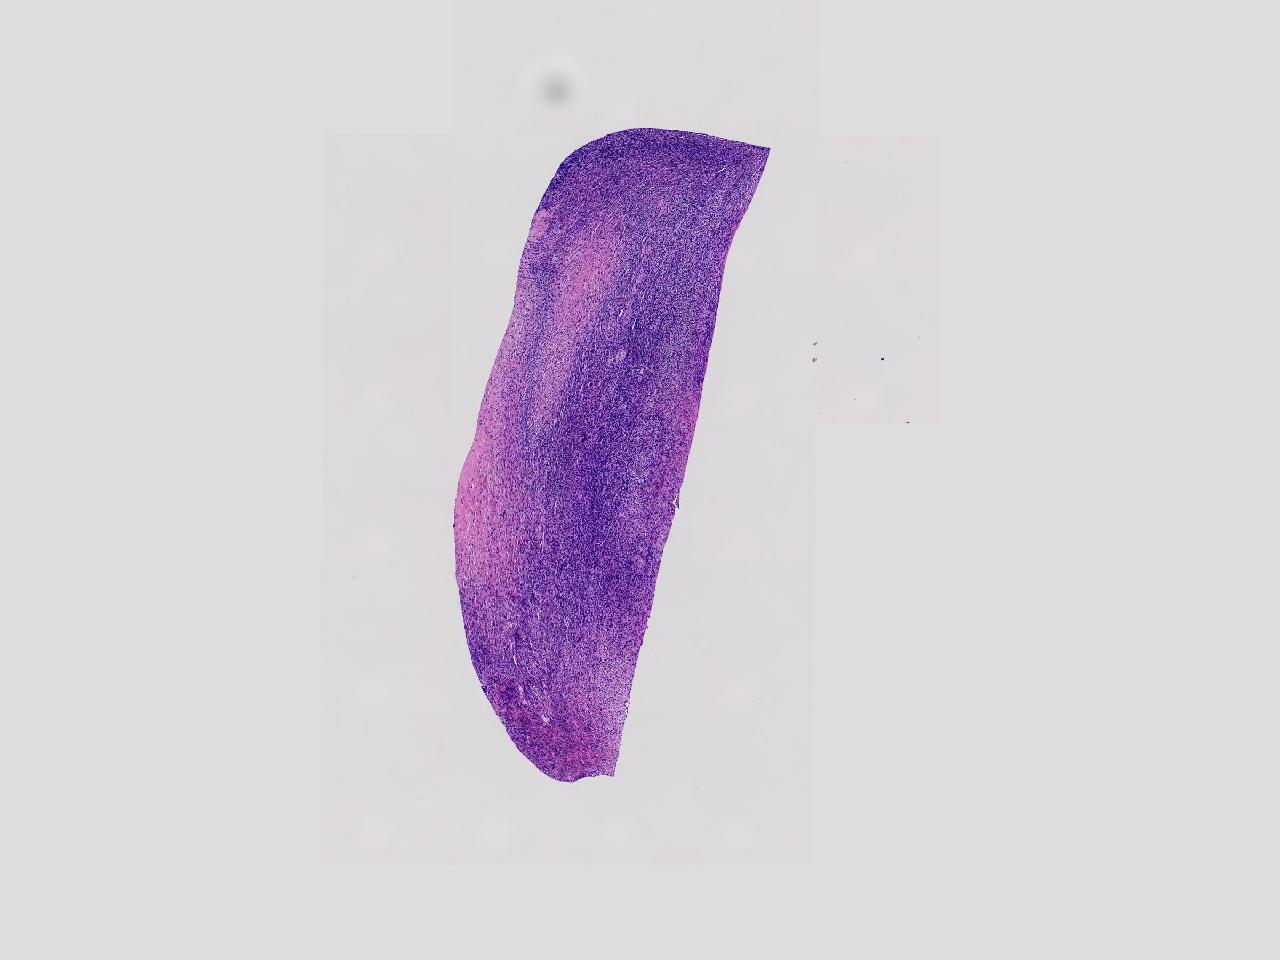

卵巢颗粒状突起活检。

女,34岁。右侧输卵管 异位妊娠,宫腔镜下见左侧卵巢颗粒状突起,取活检1块。

左侧卵巢颗粒状突起活检

灰白色不整形软组织1块,至今0.2厘米。

妊娠黄体瘤? 卵巢间质增生?

未见妊娠黄体瘤改变,见卵巢间质纤维增生。

卵巢间质纤维增生